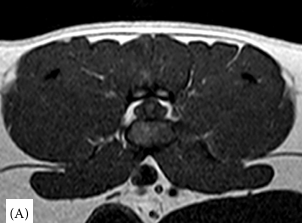

연구 대상은 4세 장모 고양이로 갑작스러운 좌측 후지 절뚝거림과 점프 회피 증상을 보였다. MRI 검사 결과, L6–L7 추간판이 원외측으로 탈출해 신경근을 압박하고, 국소 염증을 동반한 사실이 밝혀졌다. 이는 지금까지 개에서만 드물게 보고된 질환으로 고양이에서는 최초 사례다.

치료 과정에서 일반 소염제는 효과가 없었으나 프레드니솔론(스테로이드) 치료를 통해 15일 만에 임상 증상이 완전히 소실되며 성공적인 회복을 보였다. 이는 고양이에서 수술 없이도 보존적치료로 호전될 수 있음을 보여준 중요한 임상적 의미를 가진다.